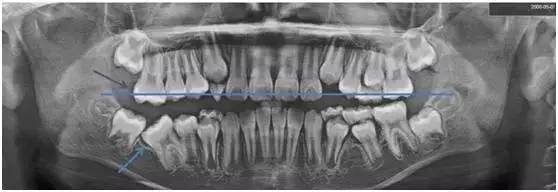

一看!果然右下“六龄齿”阻生(如图蓝色箭头处),我们向家长提出建议,必须进行早期治疗。

了解了“六龄齿”重要性之后,我们再回头看看小姑娘的X光片。

从X光片可以看到,小姑娘右下阻生的“六龄齿”,它的对合牙没有咬合接触,已经开始伸长。(以蓝色线为对标,紫色箭头指向的右上对合“六龄齿”较长)

再不处理,会占据右下阻生“六龄齿”的萌出空间,将来矫正难度将明显增大。